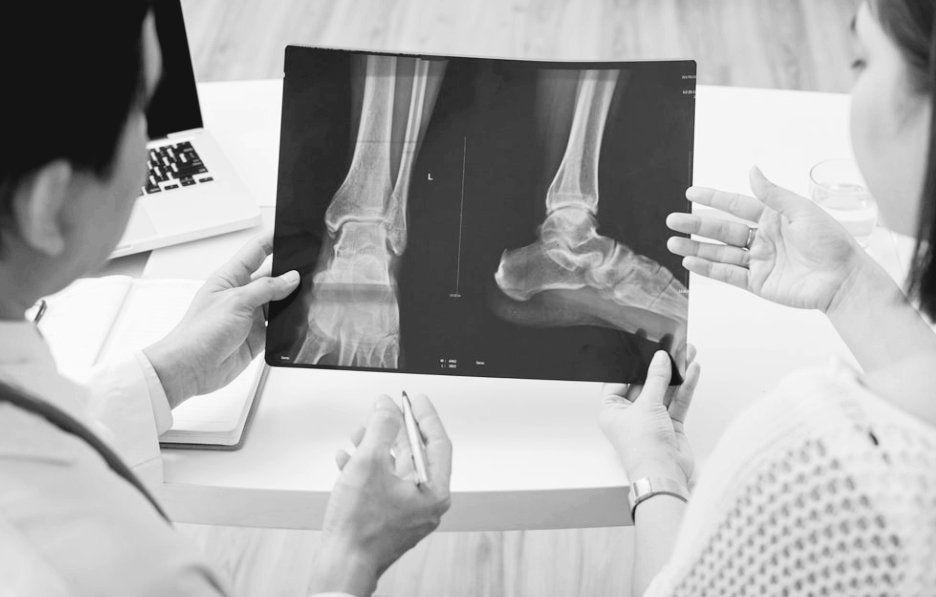

하지만 실제로 골절된 뼈를 수술 없이 확인할 수 있게 되자...

의학의 판도가 완전히 바뀌었습니다

수술 전 정확한 진단 가능

총알이나 파편 위치 확인

생명을 구하는 시간이 단축됐어요